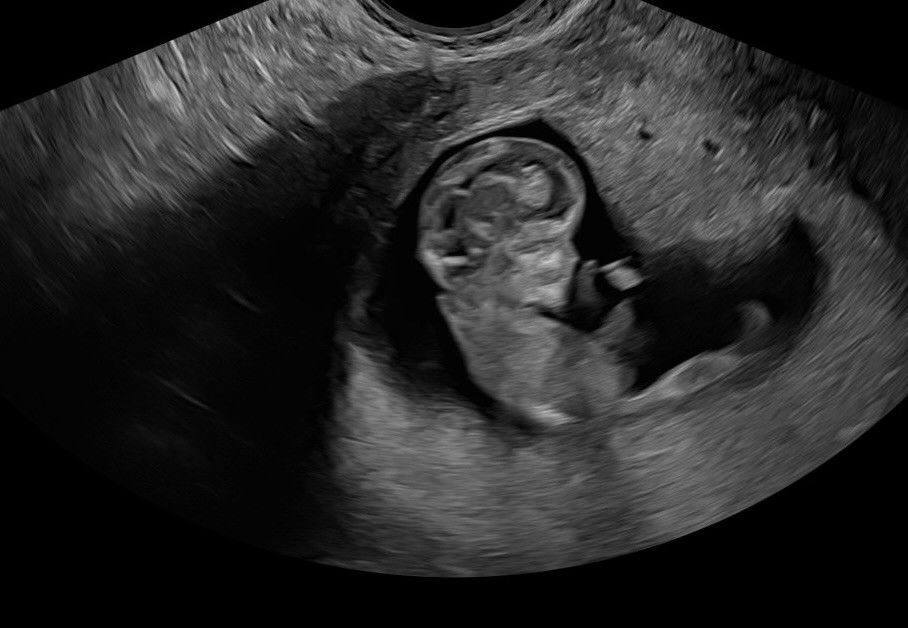

Got to see our little baby today! Measuring right on track, 7 weeks 1 day, and saw a beautiful little heartbeat of 144bpm! ❤️ I’m so relieved, we still have weeks to go to be out of the first trimester, but we never got to see the heartbeat with our previous loss.